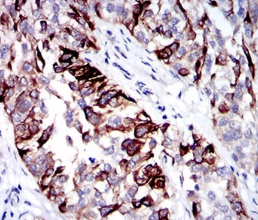

CK5 Mouse Monoclonal antibody[101E6]

IHC    1/200 - 1/1000